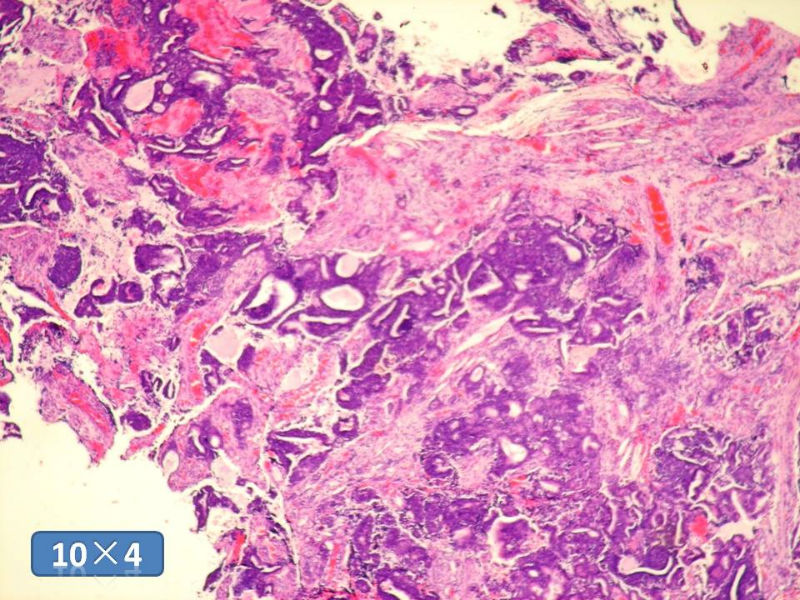

男性,49岁,间断左鼻腔出血3个月。

标签:是嗅母么?

1)嗅神经母细胞瘤?

2)腺肌上皮癌?

3)肌上皮癌?

4)神经内分泌癌?

5)腺样囊性癌?

6)其他?

腺肌上皮癌

感觉要排除畸胎癌肉瘤。

间质为恶性梭形细胞成分,其间感觉是腺体,两种成分密切相关....

免疫组化S-100的阳性区域方式...嗅母可能性大。

支持嗅神经母细胞瘤(伴有腺体分化)